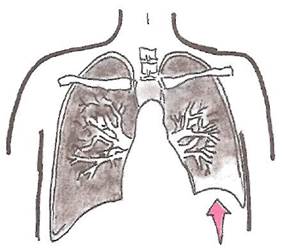

При парапневмонических выпотах средостение смещается в здоровую сторону. При опухолевых плевральных выпотах, сочетающихся с обтурационным ателектазом, который локализуется на стороне выпота, средостение смещается в сторону пораженного легкого (рис. 19).

При правостороннем парапневмоническом плеврите средостение смещается влево. При этом верхушечный толчок может локализоваться на уровне передней аксиллярной линии (рис. 19, а). В этих случаях отмечается выраженная тахикардия до 120-140 в мин, появление акроцианоза и других признаков сердечной недостаточности.

Левосторонний экссудативный плеврит сопровождается смещением правой границы относительной тупости сердца вправо (рис. 19, б). При значительных смещениях средостения вправо может произойти перегиб нижней полой вены в месте перехода ее через диафрагму, в результате чего резко ограничивается венозный возврат крови к сердцу, снижается ударный объем и сердечный выброс, развивается стойкая артериальная гипотензия.

Рис. 19. Смещение средостения при правостороннем (а) и левостороннем (б) плевральном выпоте.